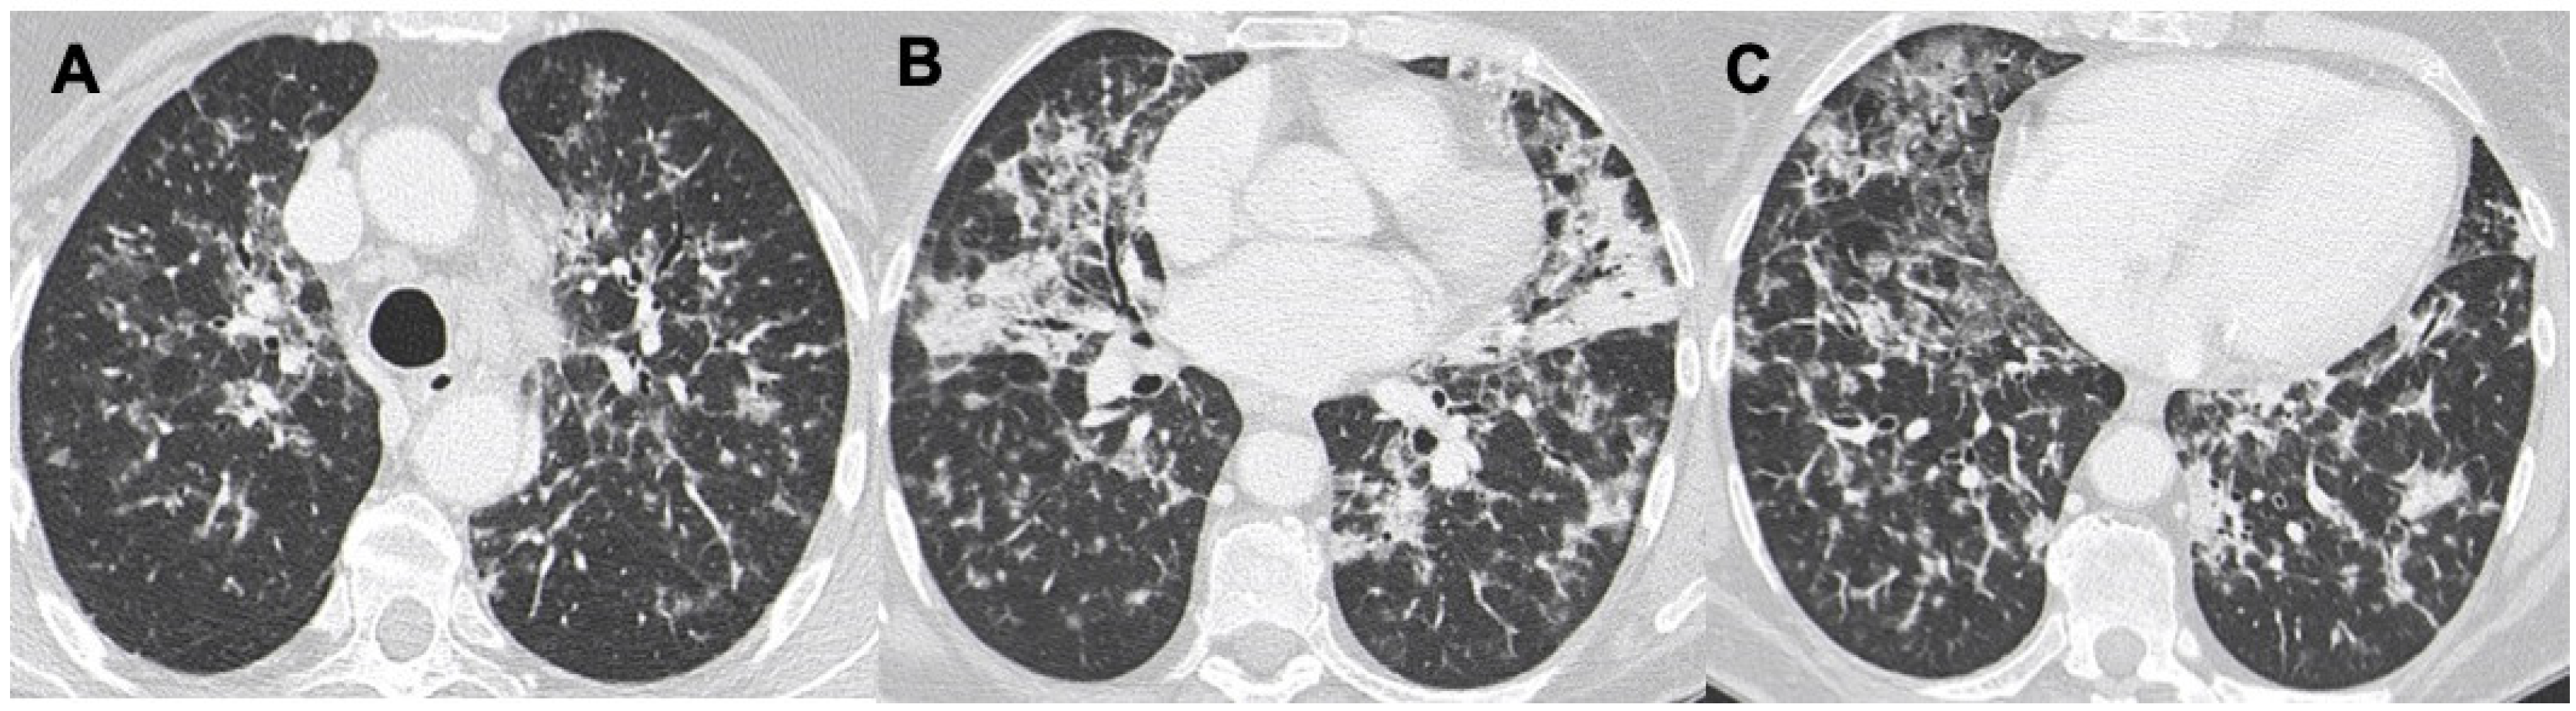

3.4. Interstitial Involvement

| LIP | Air-filled cysts, “halo sign”, masses and nodules with centrilobular appearance, GGO, patchy interstitial involvement | Infections, metastasis, neoplasm, MALT, sarcoidosis, amiloidosis |

| NHL | Nodule (usually single) < 2 cm; less frequently mass or consolidation, air bronchogram± | Infections, neoplasm, metastasis, MALT |

| LYG | Masses and nodules with peribronchovascolar distribution, basal predominance, GGO, “halo sign”, “reverse halo sign” | Vasculitis, sarcoidosis, neoplasms, metastasis, PTLD, angioinvasive aspergillosi, DLBCL |

| PTLD | Nodules, masses or consolidations (rare), ±air bronchogram, “halo sign”, perilymphatic distribution; mediastinal nodes enlargement; interstitial thickening | Angioinvasive aspergillosis, LYG |